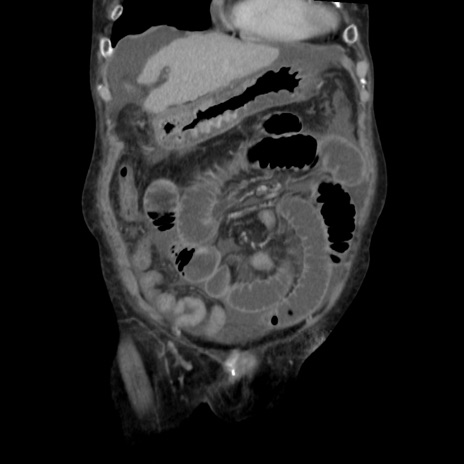

横断像

【症例】80歳代 女性

【主訴】腹部膨満感

【現病歴】他院にて肝硬変にてフォロー中。1週間前から便秘、腹部膨満感、臍部腫瘤あり受診となる。

【既往歴】肝硬変

【身体所見】腹部膨隆あり、皮膚変化なし、疼痛なし。

【データ】WBC 4600、CRP 0.25